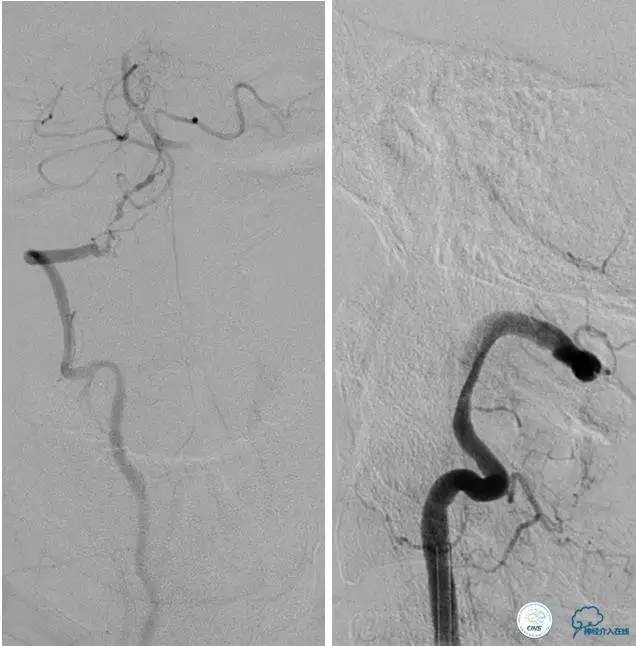

▼DSA示右侧椎动脉发育低下,弥漫性狭窄,可以看到左侧椎动脉反流,因此判断左侧椎动脉V4段CTO。

治疗:

微导丝穿过闭塞段,微导管造影,球扩闭塞段,置入Wingspan支架,血流完全恢复正常。

患者术后2天再次出现卒中发作,药物治疗好转,此后病情稳定。半年后复查DSA,见支架闭塞,侧支循环开放。患者一般情况好,mRS:1分。

▼首先行颈动脉CTO开通术,手术顺利,Wallstent支架。

▼1周后行右侧椎动脉V4段CTO开通术。

▼微导丝穿过狭窄段,微导管造影,小球囊预扩张,2mm。

▼根据血管情况选择较大球囊再次预扩张。

▼置入2枚Wingspan支架,手术成功。